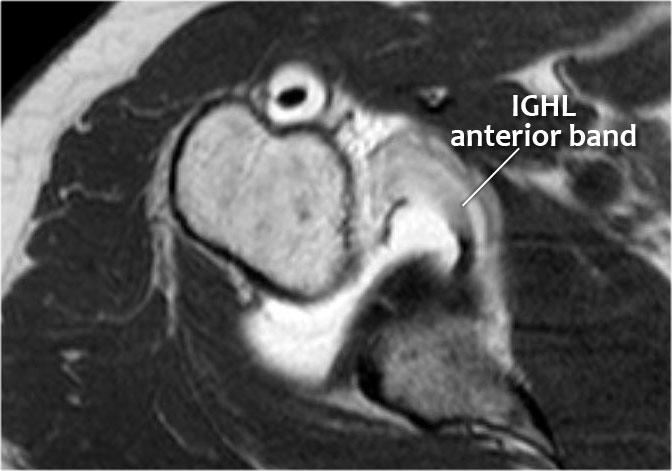

Hình MRI khớp cản từ mặt phẳng đứng dọc cho thấy sự lan rộng lên trên của đường rách Bankart.